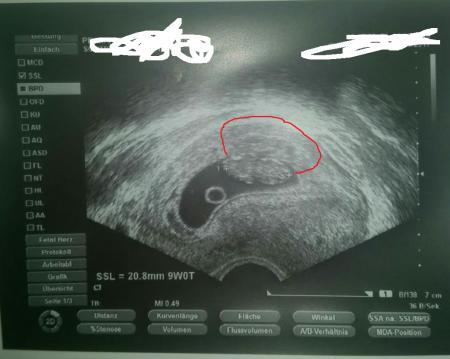

Ich hab mir jetzt mal mein letztes Ultraschallbild genauer angeschaut. Dabei ist mir aufgefallen das über dem Würmchen etwas ist, was fast die selbe Form hat, nur etwas schmaler und länglicher. Könnte das ein versteckter Zwilling sein`? Ich hoffe ihr seht es, füge in die Kommentare noch ein Bild ein, auf dem ich es grob umrandet hab, was ich meine. Das Bild ist bei 9+0 entstanden und aktuell bin ich bei 11+6

Sooo grob umrandet

nein das sind keine Zwillinge ist auch ausserhalb der Gebärmutter der Arzt würde sowas übrigens sehen und sagen (kann passieren dass ein Zwilling erst später entdeckt wird, aber heut zu tage kaum noch und wenn es auf dem Bild für einen Laien zu sehen ist, dann für den Arzt erst recht ;) )

Ne das sind keine zwillinge. War bis zu 11 ssw mit welchen schwanger und das siehst du auf dem US. Mir sagte man das ab der 8 ssw eigl die zwillinge erkannt werden und das was du meinst sieht man eindeutig. Zumal er den Herzschlag gesehen hätte

Ist doch nicht mal in einer Fruchtblase... Ganz sicher kein Zwilling. LG Lilly